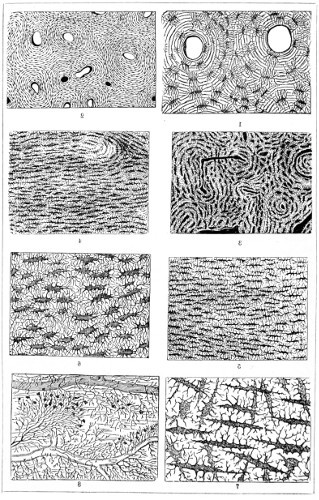

Fig. 1. Cocci, singly, and varying in size—2. Cocci in chains or rosaries (streptococcus)—3. Cocci in a mass (staphylococcus)—4 and 5. Cocci in pairs (diplococcus)—6. Cocci in groups of four (merismopedia)—7. Cocci in packets (sarcina)—8. Bacterium termo—9. Bacterium termo × 4000 xxi (Dallinger and Drysdale)—10. Bacterium septicæmiæ hæmorrhagicæ—11. Bacterium pneumoniæ crouposæ—12. Bacillus subtilis—13. Bacillus murisepticus—14. Bacillus diphtheriæ—15. Bacillus typhosus (Eberth)—16. Spirillum undula (Cohn)—17. Spirillum volutans (Cohn)—18. Spirillum choleræ Asiaticæ—19. Spirillum Obermeieri (Koch)—20. Spirochæta plicatilis (Flügge)—21. Vibrio rugula (Prazmowski)—22. Cladothrix Försteri (Cohn)—23. Cladothrix dichotoma (Cohn)—24. Monas Okenii (Cohn)—25. Monas Warmingii (Cohn)—26. Rhabdomonas rosea (Cohn)—27. Spore-formation of Bacillus alvei—28. Spore-formation (Bacillus anthracis)—29. Spore-formation in bacilli cultivated from rotten melon (Fränkel and Pfeiffer)—30. Spore-formation in bacilli cultivated from earth (Fränkel and Pfeiffer)—31. Involution-form of Crenothrix (Zopf)—32. Involution-forms of Vibrio serpens (Warming)—33. Involution-forms of Vibrio rugula (Warming)—34. Involution-forms of Clostridium polymyxa (Prazmowski)—35. Involution-forms of Spirillum choleræ Asiaticæ—36. Involution-forms of Bacterium aceti (Zopf and Hansen)—37. Spirulina-form of Beggiatoa alba (Zopf)—38. Various thread-forms of Bacterium merismopedioides (Zopf)—39. False-branching of Cladothrix (Zopf).